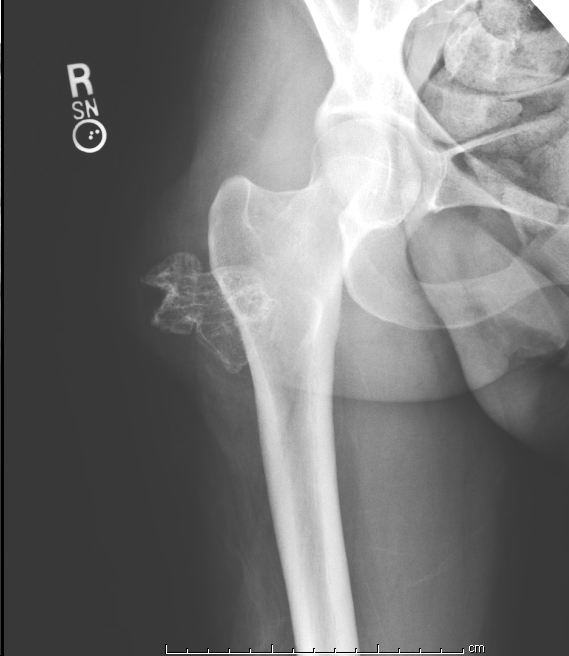

Рентгеновские снимки: Синовит тазобедренного сустава